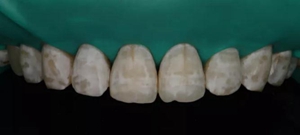

2,使用紅標45μm微米和黃標25μm粒度車針仔細緩慢打磨去除釉質(zhì)表面高氟鈣化的斑塊和釉質(zhì)凹坑0.05-0.1mm后,車針打磨后要再使用低速慢機用矽粒子拋光去除釉質(zhì)表面浮釉(松風矽粒子、樹脂拋光輪),下圖是微打磨后。

(下圖是上頜打磨后與下頜術前未研磨對比,區(qū)分打磨效果和目的)

術后顯示,滲透樹脂恢復了天然牙釉質(zhì)的折光率(天然通透牙釉質(zhì)折光率1.62滲透樹脂折光率是1.52)顯的很自然,很有光澤。完全是天然牙質(zhì)的顏色。